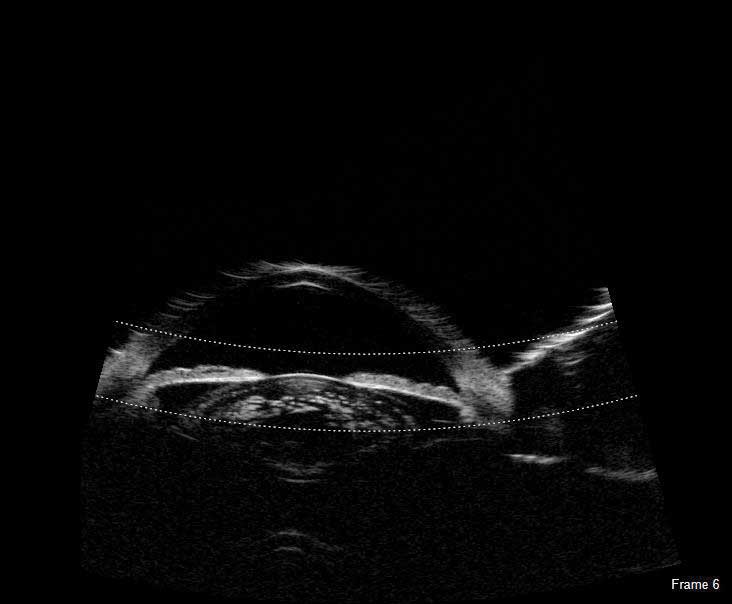

UBM

The Flex UBM probe is indispensable when obtaining high resolution images of the anterior segment of the eye, including images of structures concealed by the iris or corneal opacities.

The UBM is indispensable when imaging the anterior segment. High-resolution UBM images provide the ability to observe structures concealed by the iris or corneal opacities.

Typical applications of the high resolution images obtained with either a 35 MHz or 50 MHz transducer include sulcus-to-sulcus measurement, angle-closure, and anterior chamber pathologies. The Scanmate software provides tools for angle, area and length measurement along with an annotation tool for indicating pathologies. A water-filled single use sterile Clear Scan® Probe cover is the only component that touches the eye.

UBM Diagnostic Applications

The Flex UBM delivers clear images for the anterior segment, and the technology is presently being utilized in procedures such as:

- ACA Measurements

- Post-Lasik Corneal Evaluation

- IOL Position Monitoring

- Pre-Operative ICL Evaluation

- Diagnosis of Iris and Ciliary Cysts

- Glaucoma Post Surgery Evaluations